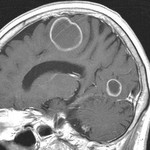

[画像診断]転移性脳腫瘍について+出血を伴う脳転移【研修医と学ぶ】 2011-02-24